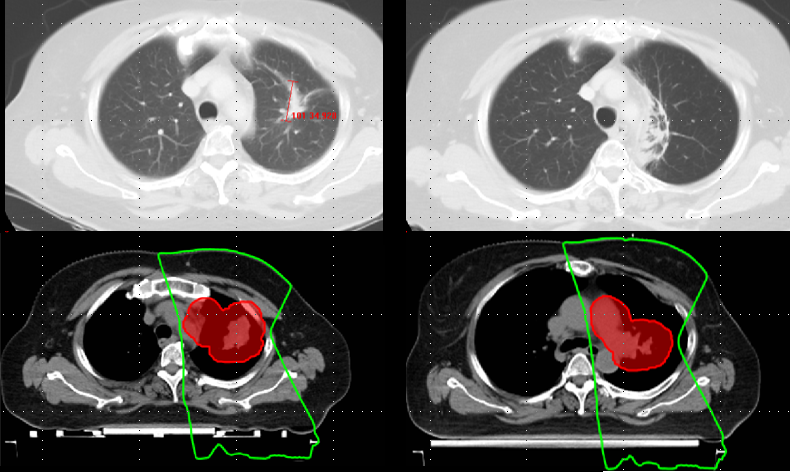

Fortunately, RT plans may be readily captured and analyzed using standardized file formats (DICOM-RT) which allows for objective assessment of targets and organs at risk. Such data may be objectively evaluated to assess RT quality, including likelihood of tumor control and toxicity, as well as providing a blueprint for subsequent evaluation of post-treatment imaging. The rigor and timeliness of RT quality assessment can be customized to meet the needs of the sponsor based on trial design, ranging from rapid review of plans prior to study treatment to passive capture of DICOM-RT data for subsequent secondary analyses, and multiple variations within.

• Differentiating between expected Radiation Induced Lung Injury (RILI) changes versus tumor progression

• Quantifying RILI in relation to time elapsed since radiation